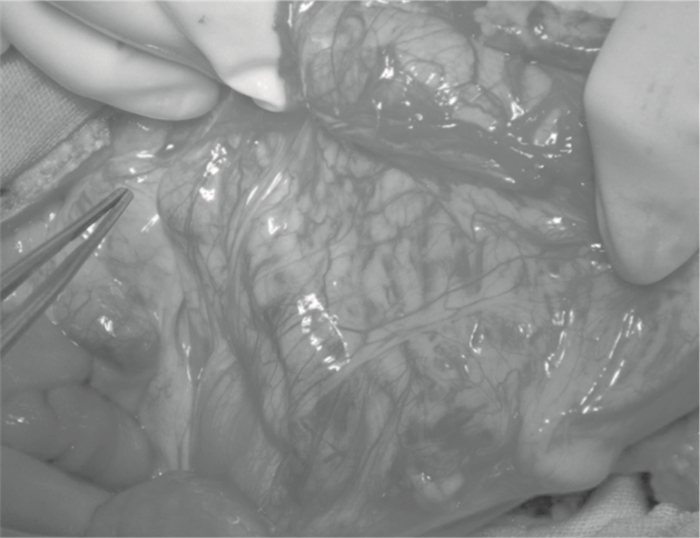

全身麻醉后,患者平臥位,肩背部墊高,頭偏向右側,頸、胸、腹皮膚消毒鋪巾。腹部手術:經腹部正中切口進入腹腔;探查腹腔粘連、結腸有無畸形、病變或血管異常等情況。首先游離結腸肝區、橫結腸和結腸脾區,并游離左右側腹膜;提起橫結腸并觀察中結腸動脈及其左、右分支。于照明充分對比度好的條件下觀察中、左、右結腸動脈的起始、走向、分支、構型、分布范圍及觸診血管搏動強弱,辨認結腸肝、脾曲區邊緣血管弓的完整性,確立代食管的結腸段主要供血管。本組105例采用左結腸動脈升支作為供血血管(1例采用中結腸動脈供血)。在結扎結腸中動脈之前,行血管夾閉試驗15 min確保選定的腸管血供充足(要注意夾閉截取腸段兩側的邊緣血管弓)。用一根帶子先測量需要結腸段的長度,然后自左結腸動脈升支起始處開始,量取相應的血管弓的長度(圖 1)。在中結腸動脈的根部切斷主干(圖 2),確保兩分支完好鏈接。